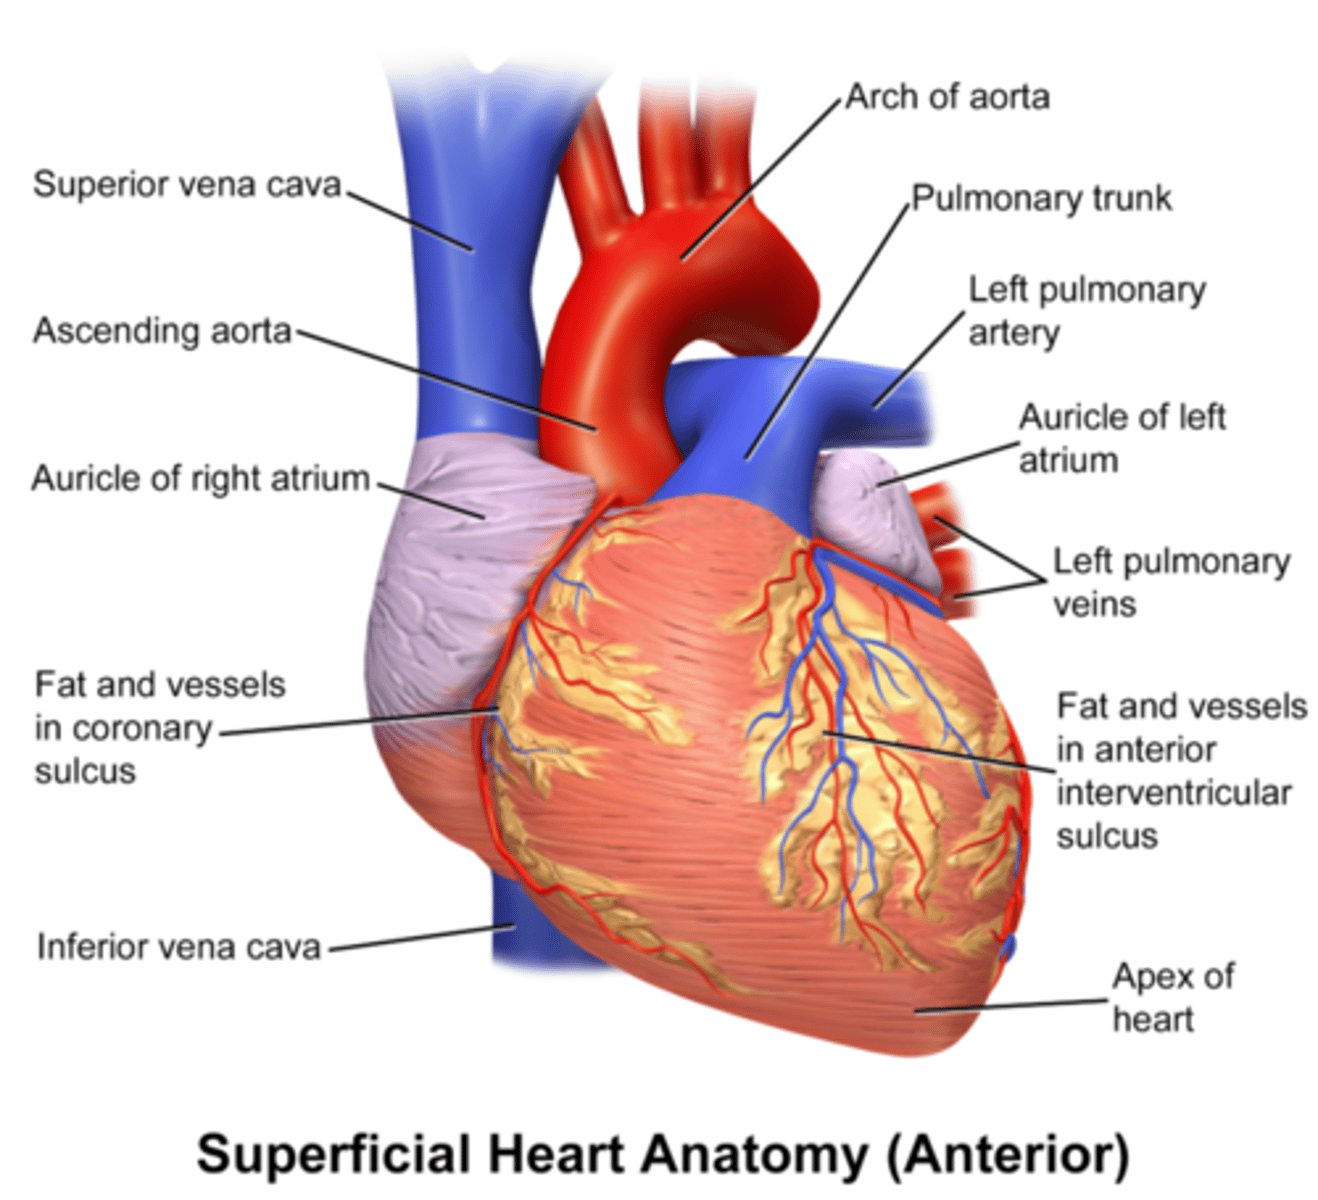

Jakie duże naczynia wychodzą z serca? Skąd dokładnie?

aorta wstępująca z komory lewej

pień płucny z komory prawej

koniuszek serca

apex of heart

Gdzie znajduje się koniuszek serca?

u dołu, po lewej stronie na wysokości 5. przestrzeni międzyżebrowej

podstawa serca

base of heart

Gdzie jest położona podstawa serca?

to tylno-górny szeroki koniec serca

Jakie powierzchnie wyróżniamy w sercu?

-przednia - mostkowo-żebrowa

-dolna - przeponowa

-płucna lewa

-płucna prawa

Jak zrotowane jest serce?

komora prawa jest najbardziej z przodu

komora lewa z lewej strony

przedsionek prawy po prawej stronie

przedsionek lewy z tyłu

Co uwypukla się z przedsionków ku przodowi?

uszka

uszko przedsionka

auricle of atrium